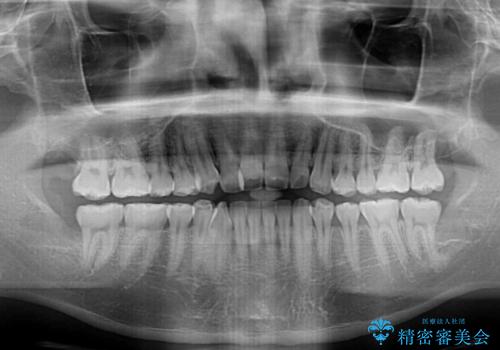

八重歯と前歯のクロスバイト ワイヤー装置で短期間矯正

- 八重歯を気にして来院された患者様です。

上顎側切歯(前から2番目の歯)が内側に転位している歯列は、インビザラインでは排列が困難であることが多いため、期間を短く、より良い仕上がりとするため、ワイヤー装置にて矯正治療を行うこととしました。